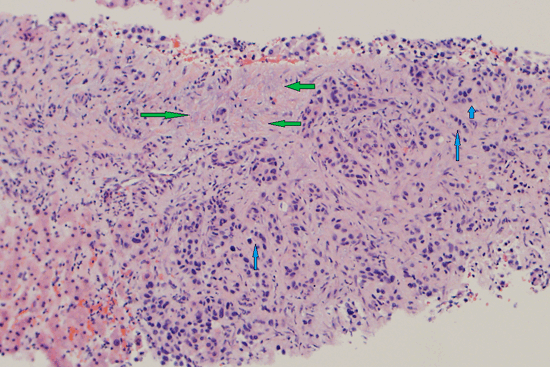

Патанатомия

Предположительно, опухоли формируются из-за повреждения клеток эпителия желчевыводящих путей (механического либо токсического). По гистологической структуре большая часть из них является аденокарциномой (опухоль, развивающаяся из железистой ткани), только 10% идентифицируют, как сквамозокарциному (плоскоклеточный рак). По своей структуре холангиокарцинома плотная, железистого строения, белого цвета, иногда мало отличается от участков, пораженных склерозирующим холангитом.